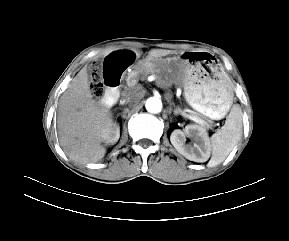

标题: CT19533:病变来源于哪?

患者,男,发现上腹部包块两月余。

病变位于肝胃间隙,实际就是位于小网膜囊(左肝下后间隙),呈轻度不均匀性强化,腹腔内及腹膜后见多发肿大淋巴结。所以我考虑肝胃间隙恶性胃肠间质瘤并淋巴结转移。

病灶强化不显著,灶周及腹膜后见多量淋巴结肿大,考虑淋巴瘤可能,其次考虑间质瘤

病灶与胰腺分界不清,来源于胰腺?

强化后病变与胃壁分界清楚,并且血供不是来源胃壁血管。考虑胰腺颈体癌并腹腔腹膜后淋巴结转移。